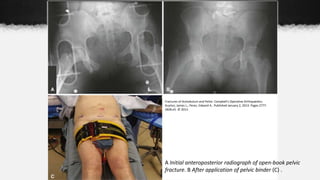

A Initial anteroposterior radiograph of open-book pelvic

fracture. B After application of pelvic binder (C) .

Stabilization

• Pelvic Binder

˗ Commercial device that can be

used for prehospital and emergent

stabilization of pelvic fractures.

˗ In APC (“open-book”) fractures,

use of a pelvic binder will close the

ring and tamponade venous

bleeding.

˗ An improvised binder can be made

using a sheet to provide

circumferential compression

around the pelvis.